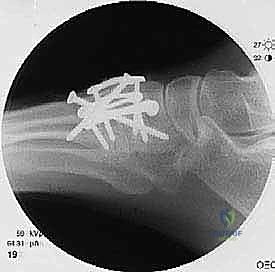

لضمان التحام العظام لتصبح عظمة واحدة صلبة، يجب تثبيتها بقوة هائلة حتى لا تتحرك أثناء فترة الشفاء. يتم استخدام مسامير معدنية متطورة (Screws)، أو شرائح معدنية خاصة (Plates)، أو دبابيس طبية متخصصة (Staples) مصنوعة من التيتانيوم الآمن على الجسم.

بعد التأكد التام من وضع العظام وثباتها باستخدام جهاز الأشعة السينية داخل غرفة العمليات (C-Arm)، يتم إغلاق الشقوق الج